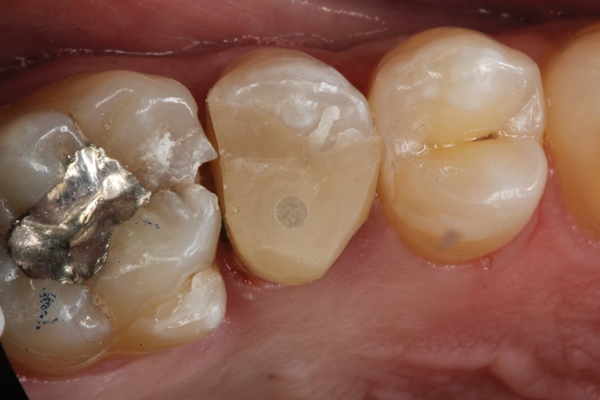

(3.) Restoration of tooth No. 31.

Figure 3

Higher viscosity bulk-fill composites can be used up to the occlusal surface, however. Two clinical cases using the bulk-fill composites Tetric EvoCeram Bulk Fill and SonicFill are presented in Figure 2 through Figure 6. Limitations when placing a high-viscosity bulk-fill composite include difficulty of condensing and esthetic restraints. Condensing a high-viscosity resin composite ensures adequate adaptation to the tooth preparation and sufficient interproximal contacts. Condensing 4 mm of composite is more difficult than condensing 2 mm. To ensure adequate interproximal contacts, a sectional or circumferential matrix with an inciso-gingival curvature can be used to obtain a tight area of contact gingival to the marginal ridge. A ring should be used to help separate the teeth and improve the tightness of the contact area.